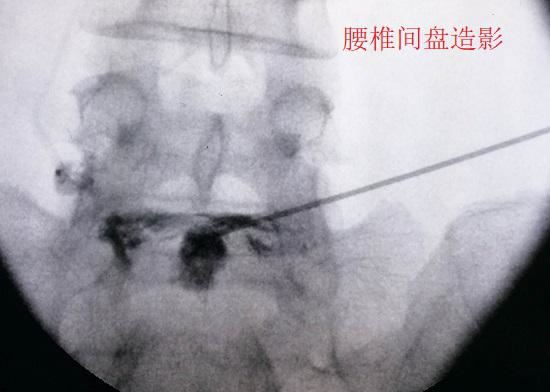

腰椎间盘内部虽然没有神经组织,但神经组织却遍布椎间盘周围每一个角懒得动减肥腰带落(包括终板以外的软骨下骨),甚至还存在于椎间盘的外层纤维环。当腰椎间盘的退北京哮喘变和损伤程度足够严重时,外层纤维环的疼痛会被诱发,周边的神经和血管组织也会顺着微小裂隙向内生长,使神经组织深入到椎间盘内部,其后果便是引发盘源性疼痛(局限于椎间盘本身的疼痛)。在对这类疼痛进行治疗时,可采取局部封闭和阻滞的疗法(在此之前还应进行其他形式的保守治疗),一般不需要扩大治疗范围。

腰椎间盘造影